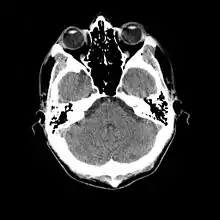

- ۱۹۸۵

- امآرآی (که در سال ۱۹۸۰ اختراع شده بود) برای نخستین بار در تشخیص نواحی مغزی مبتلا به توبروز اسکلروزیس در یک دختر مبتلا به این بیماری استفاده شد.[51]

- ۱۹۸۷

- معلوم شد که امآرآی حساسیت و اختصاصیت بیشتری نسبت به سیتیاسکن دارد. در یک مطالعه بر روی ۱۵ بیمار، امآرآی توانست در ۱۲ بیمار، ندولهای تحتاپاندیمی را که به درون بطنهای جانبی رشد کرده بود، تغییر ساختاری قشر مخ در ۱۰ بیمار (که با تکمههای تصلبی مطابقت داشت) و گشادشدگی بطنهای مغزی را در ۵ بیمار تشخیص دهد و یک تومور آستروسیتوم اثباتشدهٔ قبلی را از ندولهای تحتاپاندیمی در یک بیمار تمیز دهد.[52]

- مشخص شد که امآرآی قادر است شدت بیماری را پیشبینی کند (صرع و تأخیر تکاملی). در یک پژوهش بر روی ۲۵ بیمار، ثابت شد که رابطهای میان تعداد تکمههای قشر مغز و شدت بیماری وجود دارد. در مقابل، سیتیاسکن پیشبینیکنندهٔ مفیدی نیست، اما نسبت به امآرآی در تشخیص ندولهای کلسیفیه برتری دارد.[53]